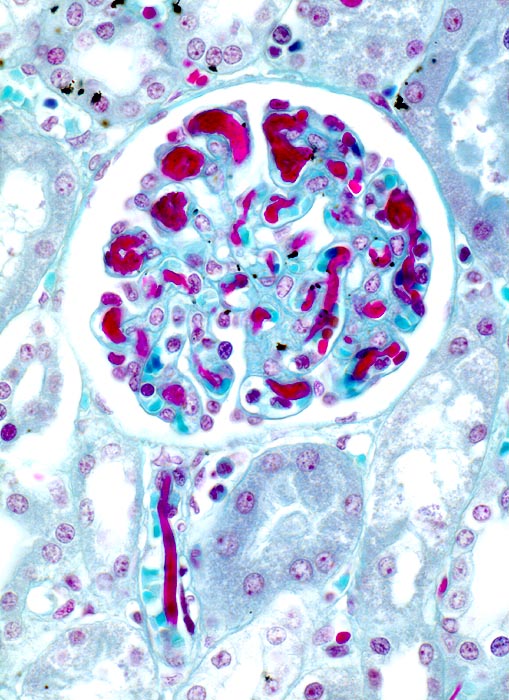

disseminierte intravasale Gerinnung

vaskulär / Durchblutungsstörung

Niere

Die Glomerulumkapillaren und das

Vas afferens sind angefüllt mit roten wurmförmigen Fibrinthromben.

Sepsis. Multiple Hämatome an druckbelasteten Hautlokalisationen. Akutes Nierenversagen.

Histologie

125